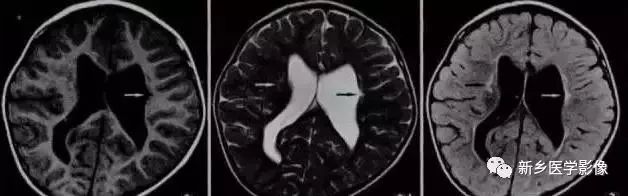

由于侧脑室周围有软化萎缩,故扩大的侧脑室外缘常不规则、不光整,这种不规则、不光整是本病引起脑室扩大的特。另外,本病均表现有脑白质量减少及脑白质内斑片状软化病灶,脑白质减少严重时表现为部分区域白质消失,脑皮层与脑室侧缘接近甚至相连。CT表现为斑片状低密度灶。MR T1WI上呈低信号,T2WI呈高信号。